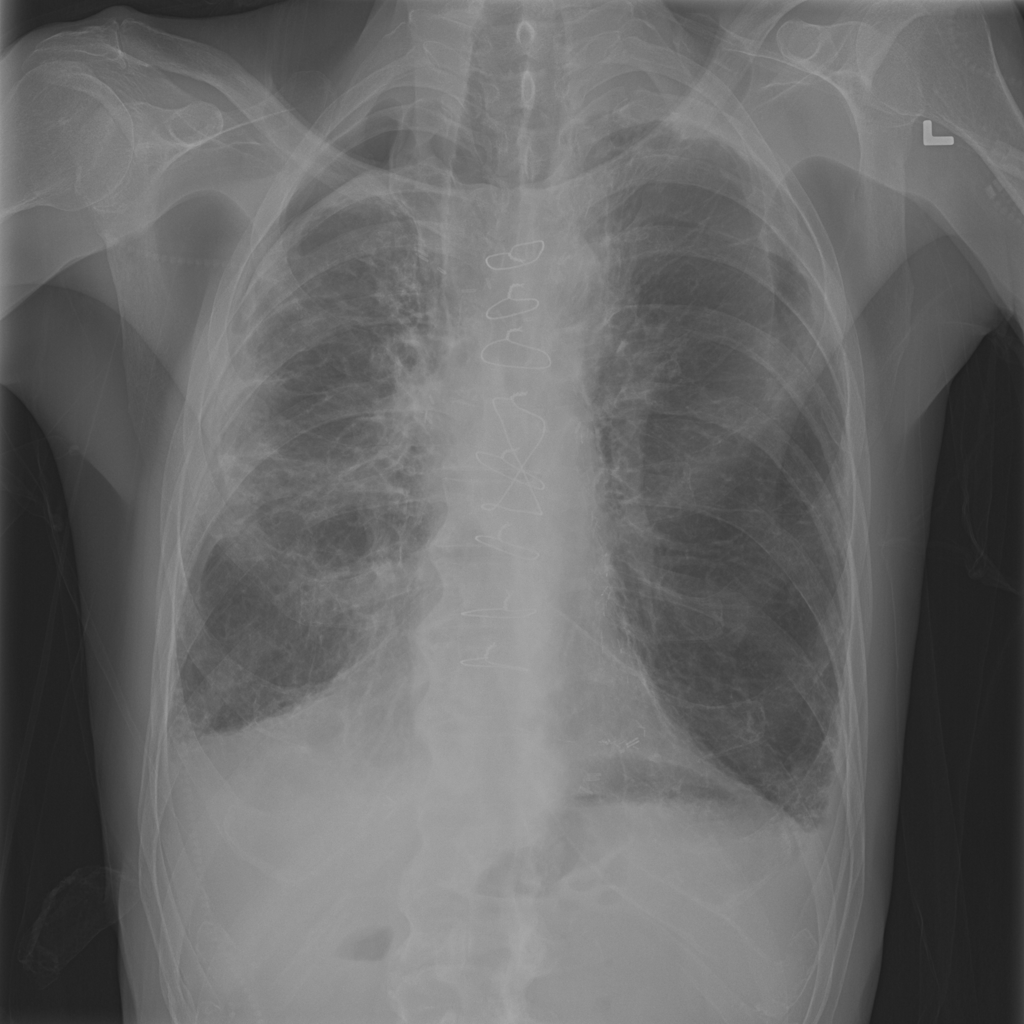

Pneumothorax

Pneumothorax means air is present outside the lung in the pleural space, which can allow part of the lung to collapse. It is an important imaging finding because the size and clinical impact can vary widely.

Showing up to 90 reference images for Pneumothorax.